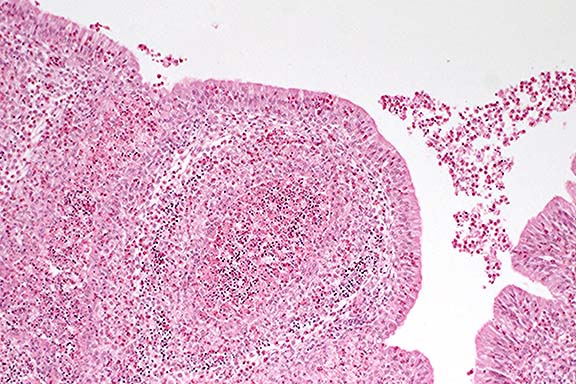

Contributor's Diagnosis and Comments: Liver and kidney: Nuclear glycogenosis, hepatocytes and renal tubular epithelial cells, goat.

Intranuclear inclusions were abundant throughout the hepatocytes and the renal tubular epithelial cells. These inclusions were large, acidophilic, and resembled viral inclusions. However, there was no appreciable cellular reaction (necrosis or inflammation) to the presence of the inclusions. Examination of the tissues by transmission electron microscopy revealed no viral particles in the nucleus, but material that was consistent with glycogen.

The accumulation of glycogen within the nucleus has been observed in humans and in animals. In humans, it is associated with diabetes mellitus, hepatitis, glycogen storage disease, other diseases, and sometimes following systemic glucocorticoid therapy. In animals, it has been observed in cases of diabetes mellitus, but more often it is considered an incidental finding in apparently healthy animals.

Case 18-2. Liver. Condensed eosinophilic inclusions in numerous hepatocyte nuclei (presumably glycogen) and moderate lipid vacuolation in the cytoplasm of hepatocytes. 40X

1. Liver, hepatocytes: Eosinophilic intranuclear inclusion bodies, diffuse, numerous, breed unspecified, caprine.

2. Liver, hepatocytes: Vacuolar change (lipid type), centrilobular, diffuse, mild.

3. Kidney, tubular epithelium: Eosinophilic intranuclear inclusion bodies, numerous.

Conference Note: Moderate postmortem autolysis hindered histologic interpretation of both organs. Participants discussed factors that help differentiate antemortem and postmortem changes. Changes that are often associated with autolysis include the absence of inflammation; diffuse changes of a similar magnitude; and increased tissue eosinophilia with loss of cellular and structural detail. This goat had renal changes that were attributed primarily to autolysis; whether acute tubular necrosis was superimposed on the other changes was not definitively determined. Mild chronic interstitial nephritis is a common finding and was not considered to be associated with the nuclear glycogenosis.

A majority of conference participants initially believed that the intranuclear inclusions were most consistent with herpesviral inclusions. However, this was ruled out by the contributor's ultrastructural findings. The periodic acid-Schiff (PAS) reaction, both with and without diastase pretreatment, did not positively stain the nuclei. The differential diagnosis also included lead or bismuth toxicity, both of which may cause intranuclear inclusions in renal tubular epithelial cells. Lead inclusions can also be found in hepatocyte nuclei, and are acid-fast. A Ziehl-Neelsen acid-fast stain performed at the AFIP was negative.